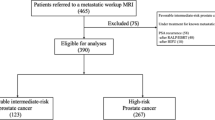

Patient selection is shown in Fig. 1.

During 2016 and 2017, 229 patients with prostate cancer underwent whole-body MRI and 161 patients aged 71 years (IQR 64–76) and with median PSA 13.0 (IQR 8–28) were eligible for analysis (Fig. 1). The indications for whole-body MRI are shown in Table 2. Intermediate- and high-risk prostate cancer were found in 36 (22%) and 125 (78%), respectively. In four patients classified as high-risk disease, a confirmatory biopsy was not obtained due to comorbidity. The PSA in these patients ranged from 22 to 2000 ng/ml. The PSA levels according to the Gleason grade groups are shown in Table 3.